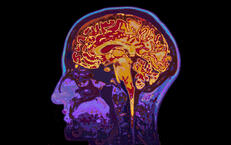

Die Behandlung von Hirntumoren hängt von verschiedenen Faktoren ab, darunter die Art und molekulare Signatur eines Tumors, seine Lage, Größe und den allgemeinen Gesundheitszustand des Patienten. Es gibt mehrere Ansätze zur Behandlung von Hirntumoren, die einzeln oder in Kombination angewendet werden können. Dies gelingt durch die enge interdisziplinäre Zusammenarbeit der Neurochirurgie mit der Onkologie (Prof. Harder, Dr. Fietz) und der Strahlentherapie (Prof. Lutterbach) im Rahmen unseres interdisziplinären Tumorboards. So kann den Patienten der Region nun eine umfassende heimatnahe Versorgung angeboten werden. Die Therapieentscheidungen erfolgen in der gemeinsamen Hirntumorkonferenz mit Strahlentherapeuten, Neurologen und Onkologen.